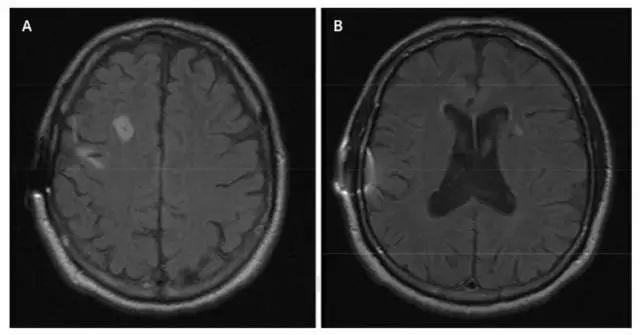

MRI沒有明顯異常。發病11年後死亡。屍檢顯示爲癡呆症的一種,皮克病(Pick’s disease)。病人額葉嚴重萎縮,顳葉中度萎縮,右側比左側病變得更嚴重。

2號病人的腦單光子發射斷層成像結果顯示,額葉血流灌注相對不足。|研究論文